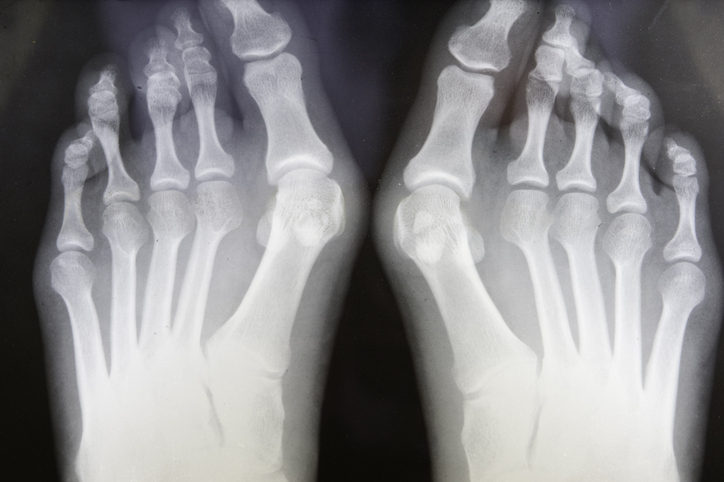

Foot and ankle surgery can be life-changing, especially for people with mobility issues. For example, surgery can make a big difference if bunions have kept you from doing the activities you love.